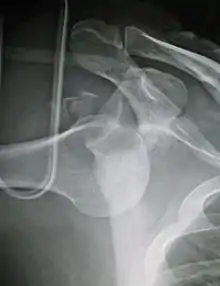

Lightbulb sign indicative of posterior shoulder dislocation shown on the left. On the right, the same shoulder after reduction.

Posterior dislocations are uncommon, and are typically due to the muscle contraction from electric shock or seizure.[6] They may be caused by strength imbalance of the rotator cuff muscles. People with dislocated shoulders typically present holding their arm internally rotated and adducted, and exhibiting flattening of the anterior shoulder with a prominent coracoid process.

Posterior dislocations may go unrecognized, especially in an elderly person[12] and in people who are in the state of unconscious trauma.[13] An average interval of 1 year was noted between injury and diagnosis in a series of 40 people.[14]